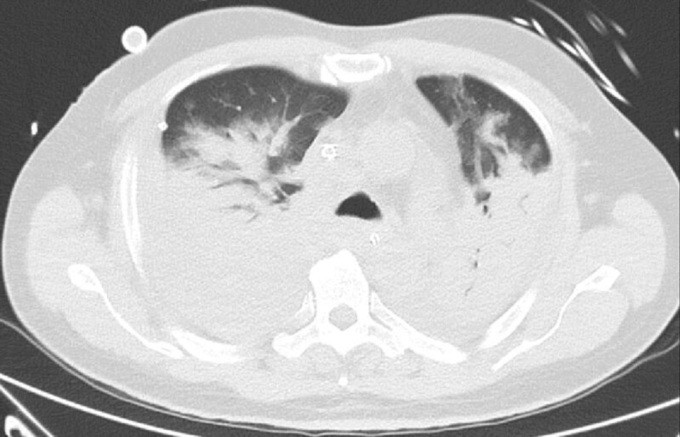

Ông Toh bắt đầu có triệu chứng từ ngày 7/3 sau khi trở về từ Thái Lan. Ông đến hai phòng khám tư để điều trị vào hai ngày sau đó nhưng không có tiến triển. Ngày 12/3, ông được đưa đến bệnh viện Khoo Teck Puat. Kết quả xét nghiệm cho thấy ông Toh dương tính với nCoV. Phổi của ông bị viêm và tràn dịch.